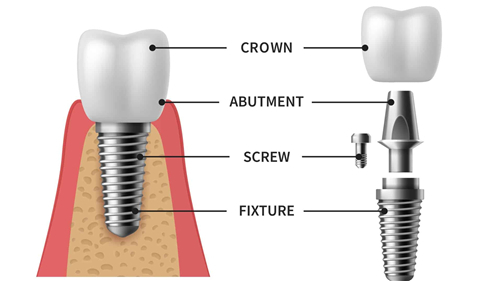

其中,种植牙技术采用的是新型的数字化导板即刻种植技术,可以让医生更正确地掌握种植牙的位置和方向,大大缩短了顾客的复诊时间,对于半口和全口种植牙手术也是一种修复结果较好的技术。

1.延庆格兰口腔种植牙价格

国产百康特种植牙:1980元起

韩国奥齿泰种植牙:2580元起

韩国纽百特种植牙:3480元起

韩国登腾种植牙:5000元起

美国皓圣种植牙:4500元起

德国ICX种植牙:5500元起

法国安卓健种植牙:6590元起

瑞士ITI种植牙:6800元起